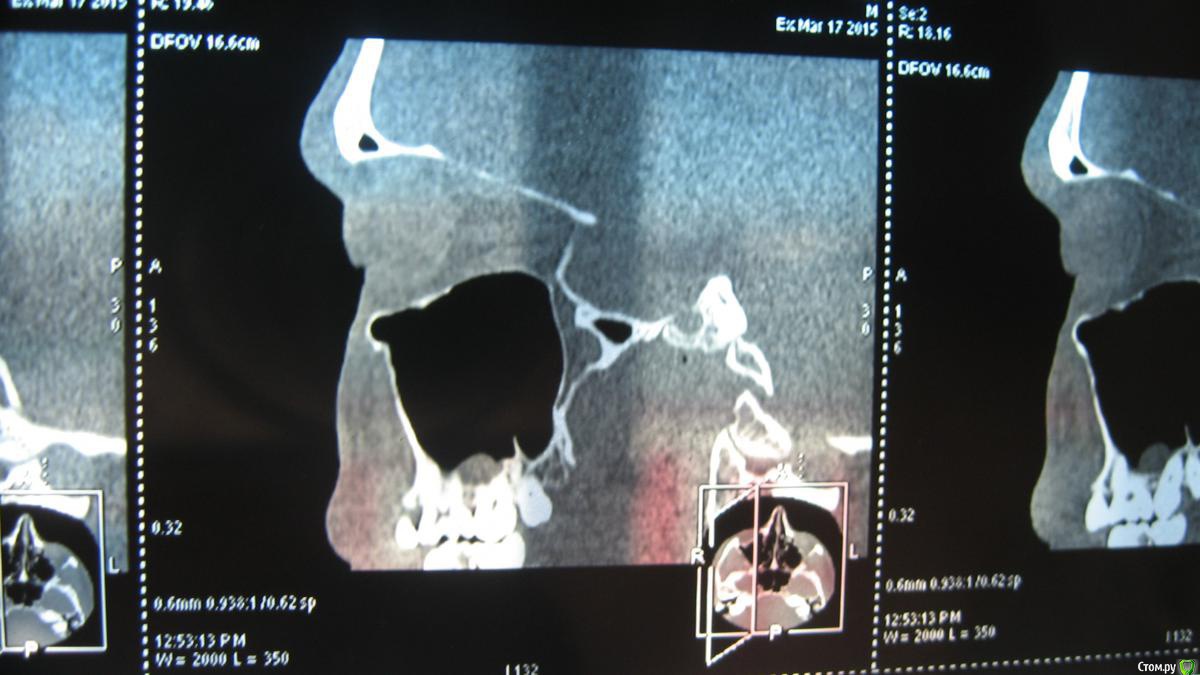

sasha35 Опубликовано 21 марта, 2015 Поделиться Опубликовано 21 марта, 2015 Здравствуйте. Осенью 2014 года лечил 4 зуб вверху. На 2 день после установки пломбы была боль, которая прошла через несколько дней. Со временем обнаружил, что больно нажимать на верхушку корня. Сам по себе не болит.Сделал снимок зуба, сходил к стоматологу. Он сказал, что плохо запломбирован канал. Я отказался вскрывать зуб. Сейчас появилась необходимость сделать СКТ ППН (для испр. носовой перегородки). Обнаружена киста в/ч пазухи, с той стороны где этот зуб(7*8мм) Сделал панорамный снимок челюсти, пошел к челюстно-лицевому хирургу. Он на снимке ничего не нашел. Тоже сказал, что зуб плохо запломбирован и возможно идет воспаление. Кисты на снимке нет. Может такое быть, на СКТ киста есть, а на рентгене нет? Выходит либо кистане связана с зубом, либо на СКТ воспаление показало как кисту? К кому мне обращаться? Ссылка на комментарий

sasha35 Опубликовано 22 марта, 2015 Автор Поделиться Опубликовано 22 марта, 2015 СКТ и рентген зуба. Панорамного снимка нет. Ссылка на комментарий